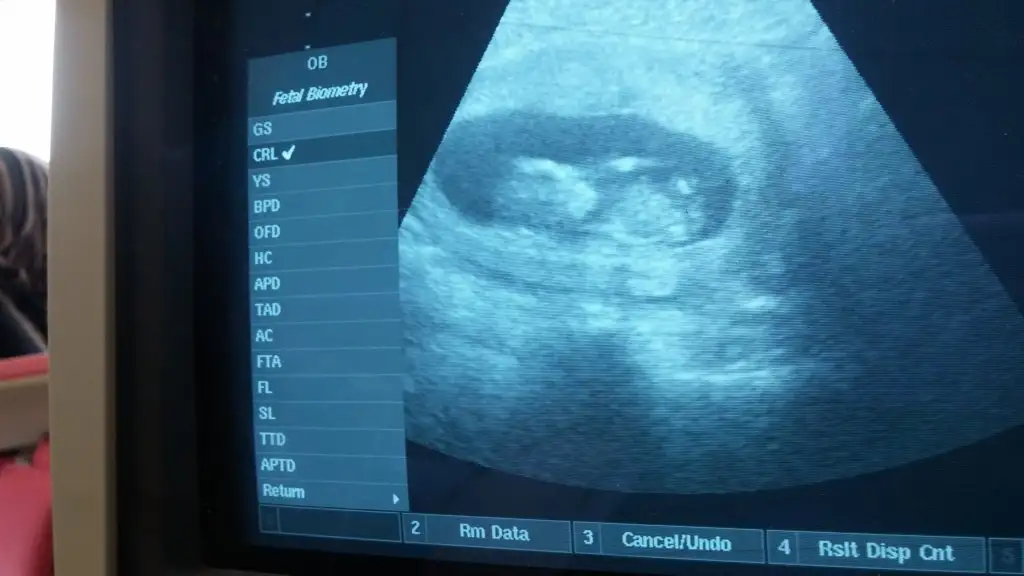

Sanki kiza benzettim benMerhaba, bugün randevumuz vardı ..goruntumuz aşağıda..10+1 haftalığız.. Belli oluyormu sizce, nedir cinsiyetimiz

erkek....Bi tahmnde bna yapablrmsnz :)

erkek...Kızlar gecen haftada paylaşmıştım karışık yorumlar geldi. Bu da bı haftaki. Yorum![]()